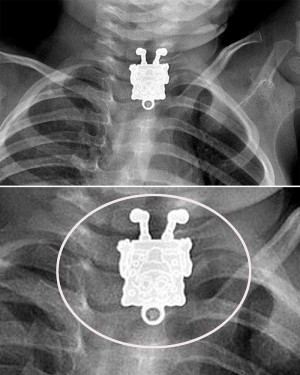

※The Telegraphで紹介された画像のスクリーンショット